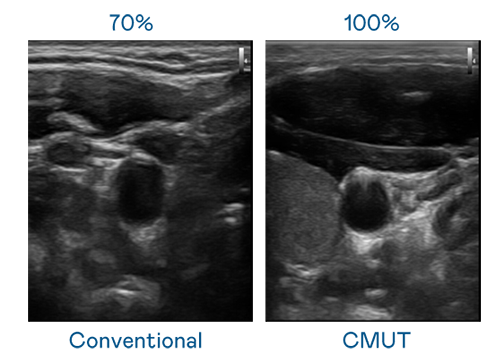

CMUT 技术是一种用电容式微机电元件来产生超音波讯号的技术。与传统 PZT 压电式技术相比,CMUT 频宽增加 30%,更宽频的超音波讯号让影像解析度大幅提升,是实现高影像品质医疗超音波扫描、促进精准医疗发展的关键技术。

大频宽带来超清晰影像

超音波影像的解析度高低,首先取决于探头能发出的讯号频宽。17c官网点击进入 CMUT 可提供高清晰的超音波讯号,提供高频宽、高灵敏度、影像纹理细节更高的超音波影像,协助医护人员缩短影像判读时间及利用精准的医疗影像进行诊断。